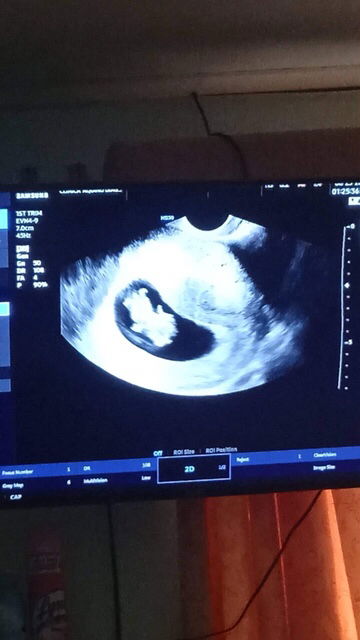

Pwede po bang tumayo ng matagal? I'm 14 weeks & 4 days preggy po & a first time mom ☺️